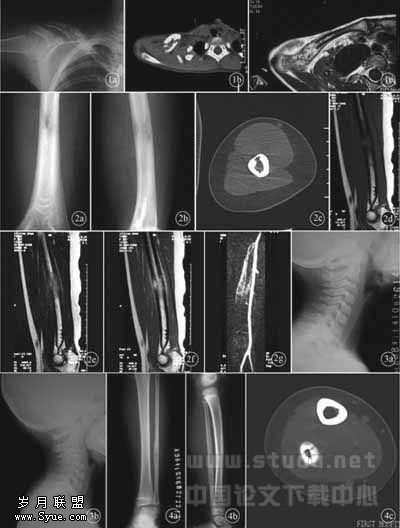

2.3 误诊的主要原因 对骨嗜酸性肉芽肿的影像学表现缺乏认识或认识不足占75.9%(22/29)(图1、图2);不恰当应用影像学检查手段占44.8%(13/29)(图3);诊断思维偏差占82.8%(24/29)(图4)。

图1 右锁骨嗜酸性肉芽肿误诊为尤文肉瘤。X线平片(1a)显示外2/3呈蜂窝状膨胀性骨质破坏,边缘不规则,可见葱皮样骨膜增生;CT(1b)示病区骨皮质小钻孔样破坏,出现软组织肿块;MRI T2WI平扫(1c)示病变呈多房性不均匀高信号及袖套征。本例误诊为骨髓炎,主要是由于对骨嗜酸性肉芽肿的影像学表现缺乏认识或认识不足 图2 右肱骨中段嗜酸性肉芽肿误诊为尤文肉瘤。肱骨中段局限性溶骨性骨质破坏,骨皮质中断,病灶边界不清,少许平行状骨膜反应(2a、2b);CT(2c)显示病变区骨皮质小钻孔样破坏,内缘呈波浪状弧形压迹;T1WI(2d)病灶信号接近肌肉信号;T2WI(2e)病灶呈较高信号;增强扫描(2f)病灶明显强化,骨膜反应呈袖套征;MRA(2g)显示血供丰富 图3 C3嗜酸性肉芽肿漏诊及误诊为结核。C3椎体早期骨质破坏(3a),因未做CT及MRI而漏诊;C3椎体骨质破坏呈楔形,邻近椎间隙变窄(3b)。本例第1张X线平片漏诊,原因是未正确应用影像学检查手段,平片观察有限度,若进行MRI检查可做出早期正确诊断 图4 右腓骨下段嗜酸性肉芽肿误诊为尤文肉瘤。腓骨下段溶骨性骨质破坏,内缘呈波浪状压迹,周围见平行状骨膜反应(4a、4b);CT(4c)显示病变区骨皮质小钻孔样的穿破及层状骨膜反应